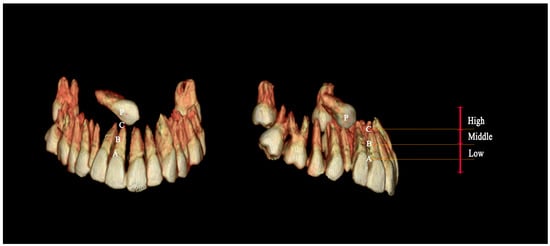

| Case Number | Impacted Canine Position | Adjacent Tooth Root Resorption | ||

|---|---|---|---|---|

| Height | Antero-Posterior | Vertical/Horizontal | ||

| 1 | High | Buccal | Horizontal | Yes (MD) |

| 2 | High | Buccal | Vertical | No |

| 3 | High | Buccal | Horizontal | Yes (MD) |

| 4 | High | Palatal | Vertical | Yes (AP) |

| 5 | High | Palatal | Horizontal | No |

| 6 | Middle | Buccal | Horizontal | No |

| 7 | Middle | Palatal | Horizontal | No |

| 8 | Low | Buccal | Vertical | Yes (AP) |

| 9 | Low | Buccal | Horizontal | Yes (AP) |

| 10 | Low | Palatal | Vertical | Yes (MD) |